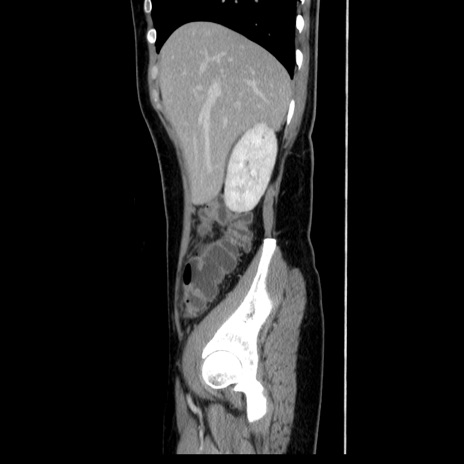

症例39(矢状断像)

【症例】40歳代女性

【主訴】上下腹部痛

【現病歴】2日目から下腹部痛あり。夜間は痛みで眠れなかった。昨日より上腹部痛と下痢が出現。臥位で痛みは軽快したため、休んでいた。本日になって臥位でも立位でも痛みが強くなってきたため救急要請。

【既往歴】子宮内膜症

【身体所見】部:平坦・軟、左上下腹部に圧痛あり、反跳痛あり。

【データ】WBC 21800、CRP 26.78

CT